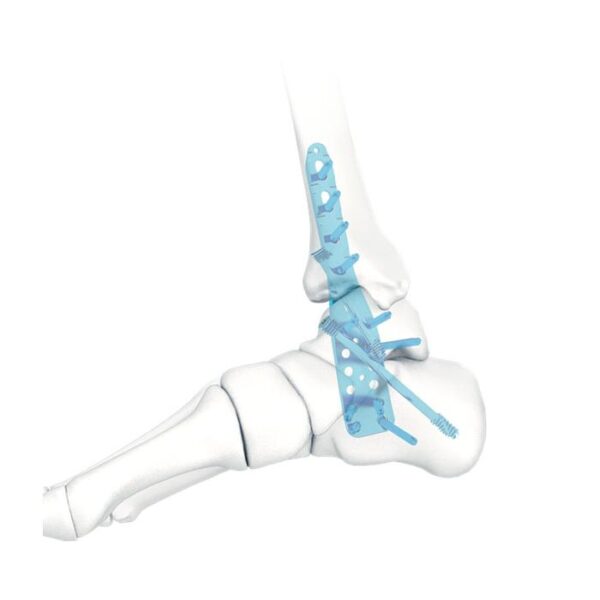

- Tres filas de orificios en el extremo distal, para fijar el calcáneo; Tornillo de fijación divergente, para mejorar la buena sujeción.

- Tres filas de agujeros en el medio, para fijar el astrágalo; tornillo de fijación divergente, para proporcionar una fijación estable

- Diseño de perfil bajo, para reducir la irritación de los tejidos blandos.

- Fusión de la articulación tibiotalar

- Fusión de tibiotalar lateral y calcáneo